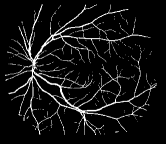

As pointed out in recent works [15, 17], a good semantic segmentation network should learn multi-level features. Further, it should have multiple stages with different receptive fields to learn more inherent features from different scales. FCN, taken as an example, uses skip connections to fuse multiple stages outputs, as well as the HED network, in which a series of side-output layers are added after each stage in VGGNet. The HED network was first proposed for edge detection, and further used for image-level vessel segmentation in recent studies [6, 16], with significant performance. However, our experimental results show that such network architecture is not appropriate for vessel segmentation directly. Figure 1 provides such an illustration. Reasons for this phenomenon are straightforward. On one hand, the side-output of the first layer often contains too many noises. On the other hand, the features produced by the last side-output layer are too coarse due to information loss of pooling operation. Obviously, the inaccurate vessel map of side-output1 and side-output4 should have negative impacts on the final segmentation result.

2.2 Bottom-top short connections

With the deepening of DSN network, the receptive field of each side-output layer gets larger, which makes the corresponding vessel map much blurrier as observed from the first row in Figure 1, especially for side-output4. These observations inspired us to pass low level fine semantic information to high levels to alleviate the blurring situation.

Bottom-top short connections aim to refine high-level segmentation results. However, we can observe from the first two rows in Figure 1 that the vessel map generated by the first side-output layer contains too many noises while the map generated by the last side-output could capture the main vessel structure. Therefore, we propose delivering high-level structural information to the first side-output layer to reduce its noises. We implemented this kind of information delivery by a top-bottom short connection from conv4 to feat_conv1, which can been seen in Figure 4. We first convolved the last convolution of conv4 using 1 convolution kernels with size 33. Then the obtained feature map are up-sampled 8 to get feat_4_1. The information (feat_4_1) passed from conv4 are concatenated with feat_conv1 to form feat_conv1_fuse (see Figure 5). At last, one hand hand, we perform a 11 convolution operation on feat_conv1_fuse to get the information (feat_1_2) delivered to feat_conv2. On the other hand, we performed convolution operation with a kernel size of 11 and sigmoid transformation for feat_conv1_fuse sequentially to obtain the segmentation result (side 1). At last, side 1 is compared with the ground truth to get the loss of the first side-output layer.

In addition, we can observe from Figure 1 that the side-output1 and side-output4 of the BTS-DSN were more accurate compared with those of the DSN.